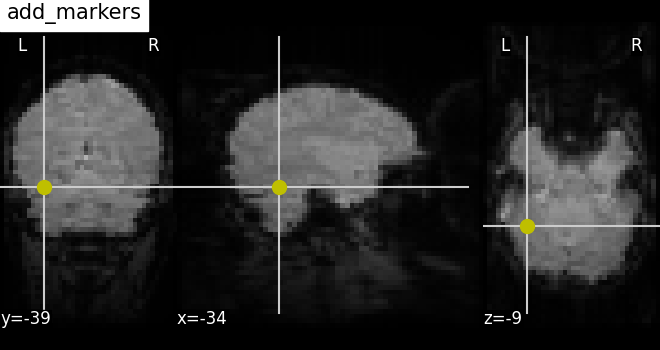

7.4. Adding overlays, edges, contours, contour fillings, markers, scale bar¶

To add overlays, contours, or edges, use the return value of the plotting

functions. Indeed, these return a display object, such as the

nilearn.plotting.displays.OrthoSlicer. This object represents the

plot, and has methods to add overlays, contours or edge maps:

display = plotting.plot_epi(...)